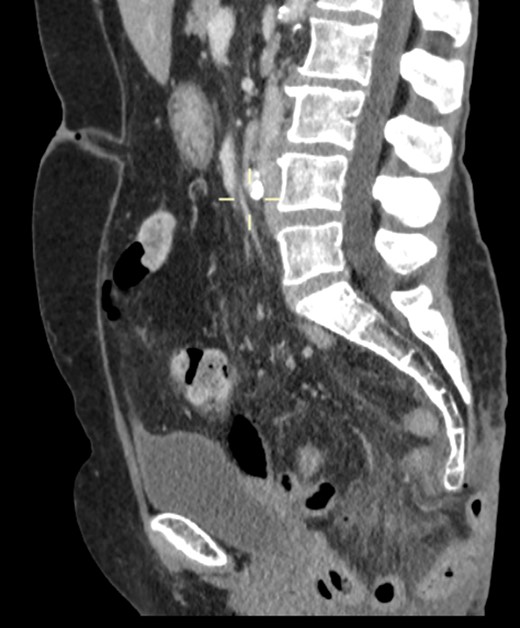

On examination, she was febrile. Her abdomen was generally tender. Bowel sounds were present and up to that time her stoma was working. Her perineal hernia was red and tender. Her initial CXR (Fig. 1) did reveal a sliver of gas underneath her right hemidiaphragm and in keeping with her abdominal findings she progressed to further imaging. CT abdomen pelvis with contrast showed pneumoperitoneum (Fig. 2) with ‘a tiny pocket of air is also seen adjacent to a loop of bowel in the pelvis posterior to the bladder’. ‘Exact site of perforation has not been demonstrated but could possibly be in the bowel loops in the perineum’ (Figs 3 and 4).

CT showing small bowel loops in pelvis with perineal hernia and free fluid.